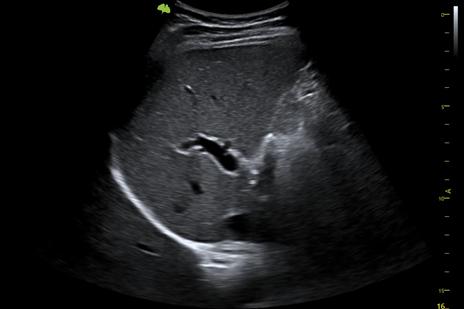

S100 có hình ảnh siêu âm mạch máu, thai nhi đều sắc nét

1. Công nghệ VLucid+

Vinno S100 mang lại hiệu suất chụp ảnh được nâng cao với công nghệ VLucid+ . Tầm nhìn được cải thiện với VLucid+ tốc độ thu thập dữ liệu nhanh hơn, nhiều chùm tin song song, hiệu chỉnh chùm tia thích ứng, khử nhiễu tín hiệu tốt hơn. Cùng với nó là công nghệ thu thập dữ liệu gấp 3 lần các chùm tia song song. Thông qua thuật toán xử lý tín hiệu thông minh của AI từ đó tạo ra tầm nhìn hiệu suất được nâng cao vượt trội